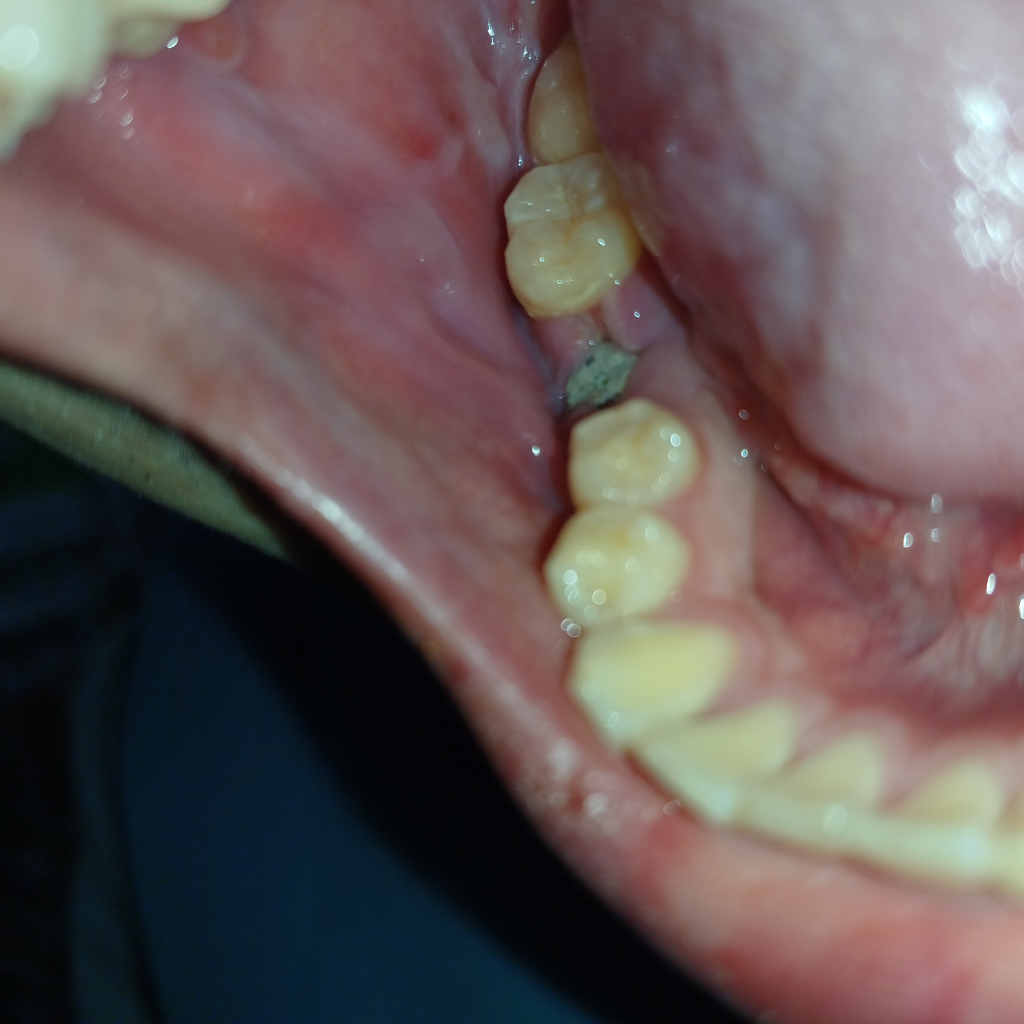

임플란트실밥풀고1주일째입니다 잇몸에 혀를 대보니까 말랑말랑 한데 괜찮은건가요

임플란트실밥풀고1주일째입니다 잇몸에 혀를 대보니까 말랑말랑 한데 괜찮은건가요 사진은 방금촬영한건데 상태는 괜찮은걸까요?

임플란트를 하고 나면 인플란트 하는 그의 잇몸이 약해져 있을 수 있습니다.

시간이 지나면 자연스럽게 아물기 때문에 혀를 가져다 대지 않는 것이 좋습니다.

크게 이상이 잇는건 아니고 잇몸이 치유되는과정중에 생기는 현상입니다. 크게 걱정은 안하셔도 됩니다.

현재 잇몸상태는 치유중인 것으로 보이고 초기 치유는 1~2주 정도 걸립니다

해당부위 구강위생관리를 철저히해주시기 바랍니다